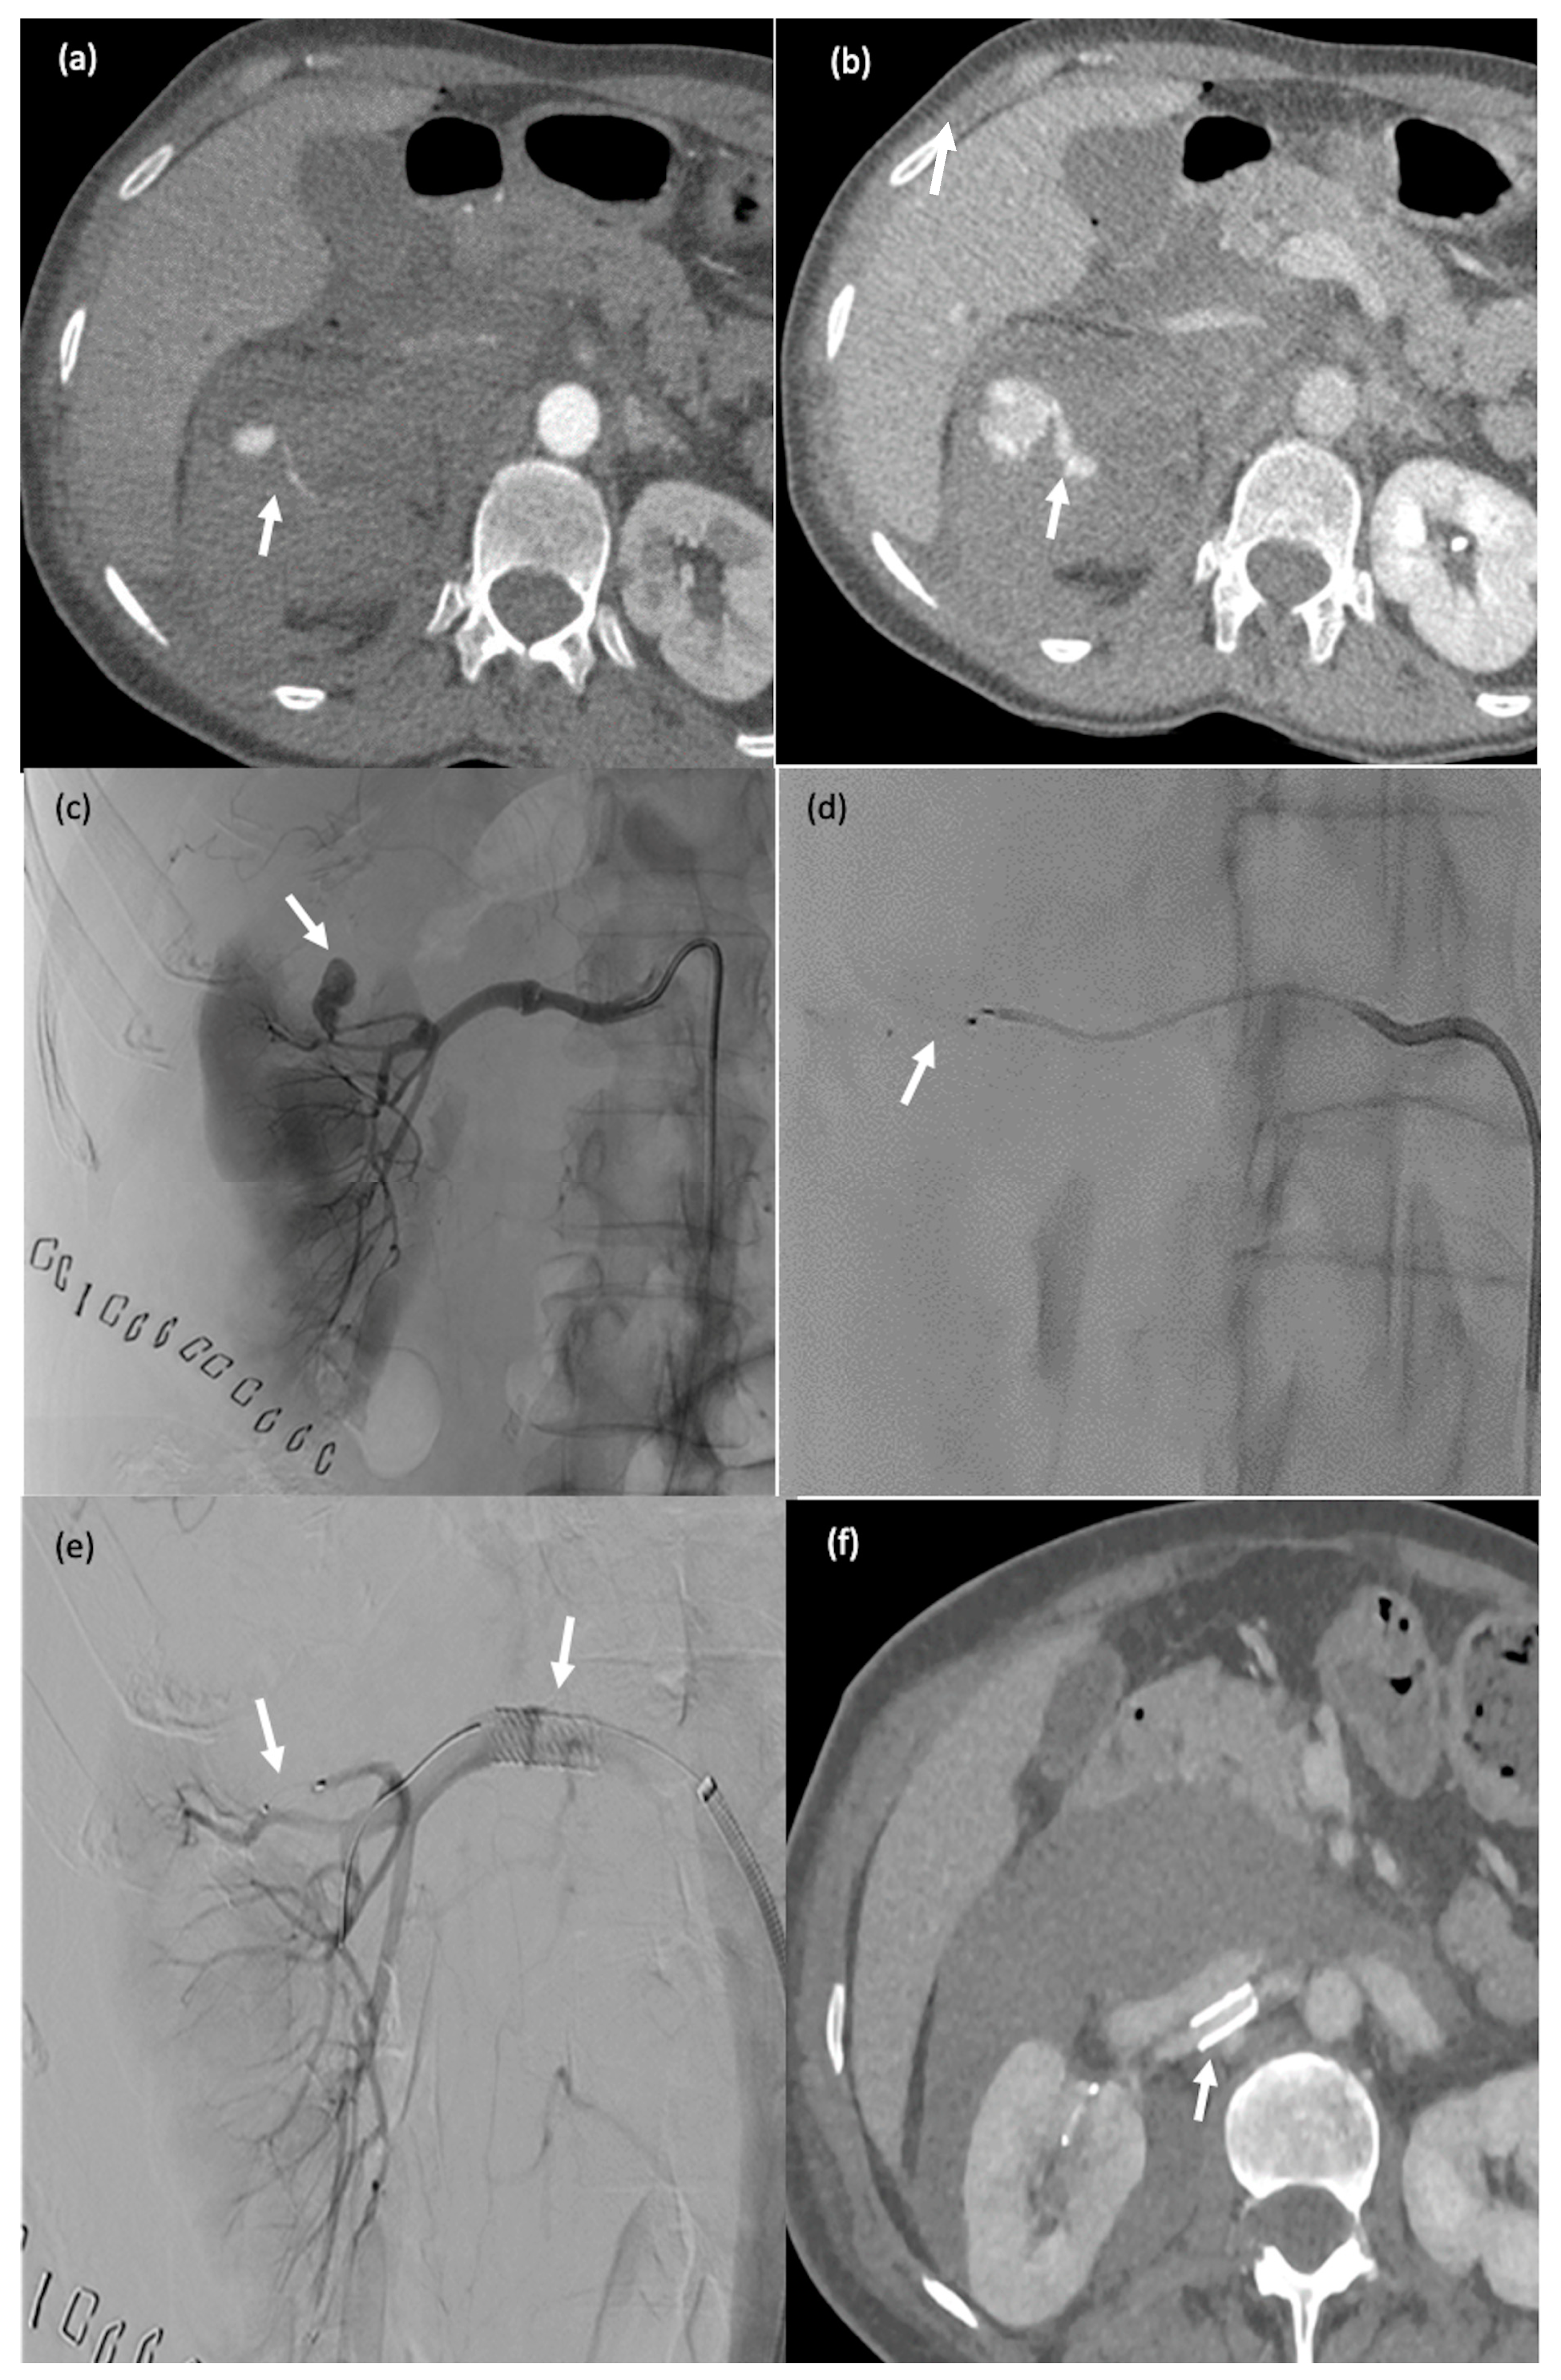

3.4. Technical Success Rate

Figure 3. A 60-year-old man (#1) with diffuse metastatic disease from colonic cancer that was unresponsive to chemotherapy and required intensification via chemotherapy port catheter implantation. (a,b) MVP-3Q implantation (arrow) to occlude the left gastric artery before insertion of the chemotherapy catheter. (c,d) Catheter insertion in the gastroduodenal artery, occlusion of the gastroduodenal artery and stabilisation of the chemotherapy catheter via implantation of 2 MVP-3Qs through a smaller microcatheter inserted in the side-whole of the chemotherapy catheter (arrows). (e,f) Computed tomography after arterial contrast medium administration showing excellent enhancement of all metastatic lesions in both liver lobes.